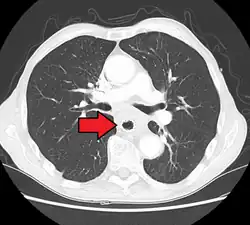

Although an occlusive tumor may be suspected on a barium swallow or barium meal, the diagnosis is best made with an examination using an endoscope. This involves the passing of a flexible tube with a light and camera down the esophagus and examining the wall, and is called an esophagogastroduodenoscopy. Biopsies taken of suspicious lesions are then examined histologically for signs of malignancy.

Additional testing is needed to assess how much the cancer has spread (see § Staging, below). Computed tomography (CT) of the chest, abdomen and pelvis can evaluate whether the cancer has spread to adjacent tissues or distant organs (especially liver and lymph nodes). The sensitivity of a CT scan is limited by its ability to detect masses (e.g. enlarged lymph nodes or involved organs) generally larger than 1 cm.[44][45] Positron emission tomography is also used to estimate the extent of the disease and is regarded as more precise than CT alone.[46] PET/MR as a novel modality has shown promising results in preoperative staging with fair feasibility and good correlation in comparison to PET/CT. It can enhance tissue differentiation with lowering the radiation dose to the patient.[47] Esophageal endoscopic ultrasound can provide staging information regarding the level of tumor invasion, and possible spread to regional lymph nodes.

Contrast CT scan showing an esophageal tumor (axial view)

Contrast CT scan showing an esophageal tumor (coronal view)